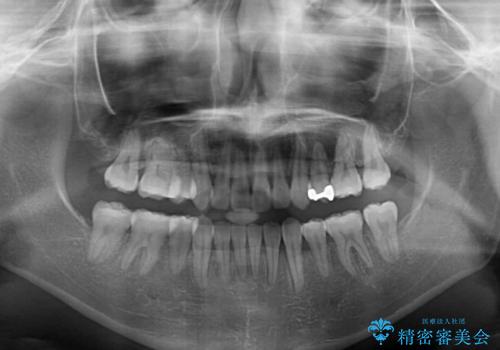

- 前歯の叢生と八重歯を気にして来院された患者様です。

叢生が強く、奥歯の咬合も左右差が大きかったため、上下左右4本を抜歯して、ワイヤー矯正を行うこととしました。

20歳前後と年齢が若かったため、非常にスムーズに歯列が整い、1年半をかけずに治療を終えることができました。